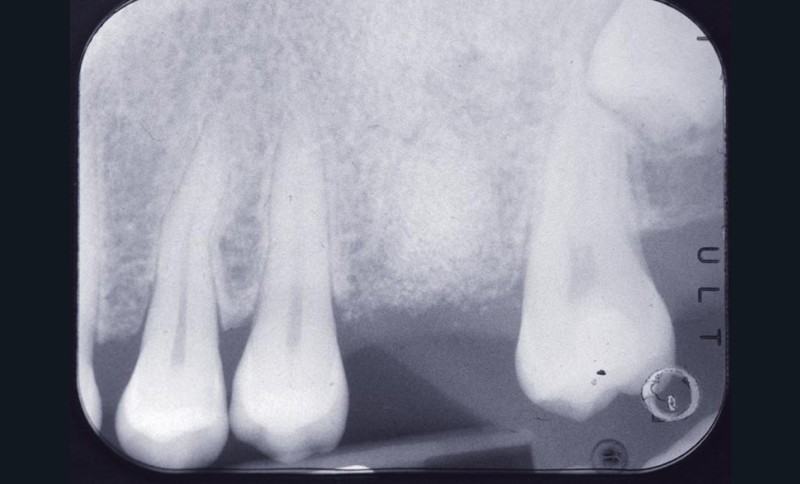

La patiente se présente au cabinet pour une fistule vestibulaire sur la 26. Elle avait subi une résection apicale qui n’avait pas eu de succès et avait provoqué une résorption de la corticale vestibulaire de l’alvéole. Le plan de traitement proposé prévoit l’extraction de la dent, le comblement de l’alvéole et du défaut avec la technique de « socket preservation » (fig. 1).